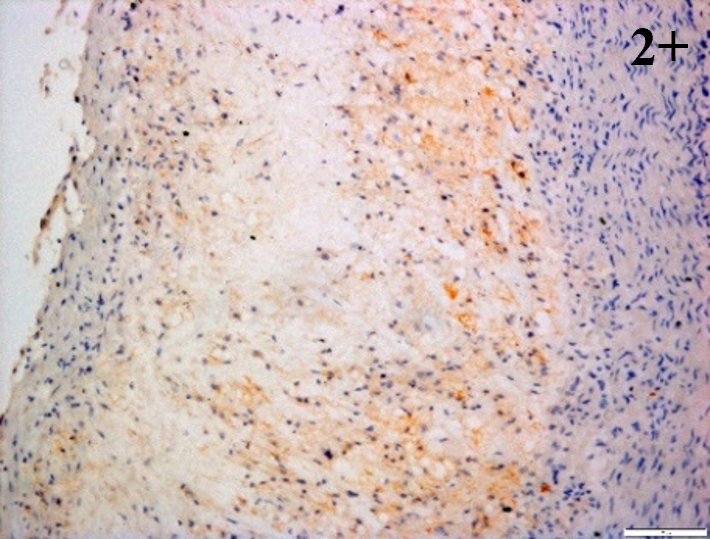

Immunoreactions of ICAM-1, VCAM-1, e-selectin, IL-6, IL-8, NF-

According to the percentage endothelial staining of cells, semi-quantitative

scores were applied. Score: 0 (negative); 1+ (1–10% positive cells); 2+

(11–25% positive cells) and 3+ (